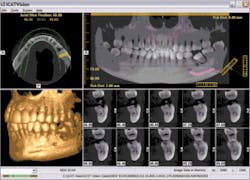

Once the scan is complete, the 3-D imaging software takes over. These 3-D images precisely replicate the positions, shapes, and measurements of every scanned facial structure, including the maxilla, mandible, TMJ, sinuses, nasal cavity, and area back to the cervical spine. Within the software, these views can be sliced and rotated for diagnostics and treatment planning. It’s like picking up a cup and looking at it from all sides instead of looking at a picture of it, and then slicing the cup any way you want to see and measure its internal structure.

Specialized procedures are particularly aided by 3-D technology. Defining the position of vital structures can help avoid complications during implant planning and placement, as well as third molar removal. For those dentists placing implants, the “nerve marking estimation tool” locates previously undetected nerve canals. The precise slices of the mandible and maxilla assist in determining implant type, size, and location.

Orthodontists can accurately pinpoint root positions, impacted teeth, supernumerary teeth, and other conditions that affect tooth movement. Clinicians who treat TMJ disorders benefit from viewing the TMJ areas from all angles. The list goes on.